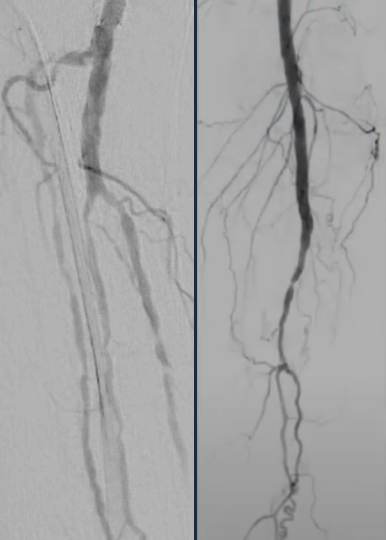

Calcified peripheral arterial disease has met its match in the new Shockwave E8 IVL catheter – our longest catheter yet. Designed for versatility, Shockwave E8’s sonic pressure waves provide a low-risk option that effectively cracks calcium where it counts, simplifying complex procedures and helping restore peripheral blood flow.

The largest prospective real-world evidence for the treatment of complex, heavily calcified PAD